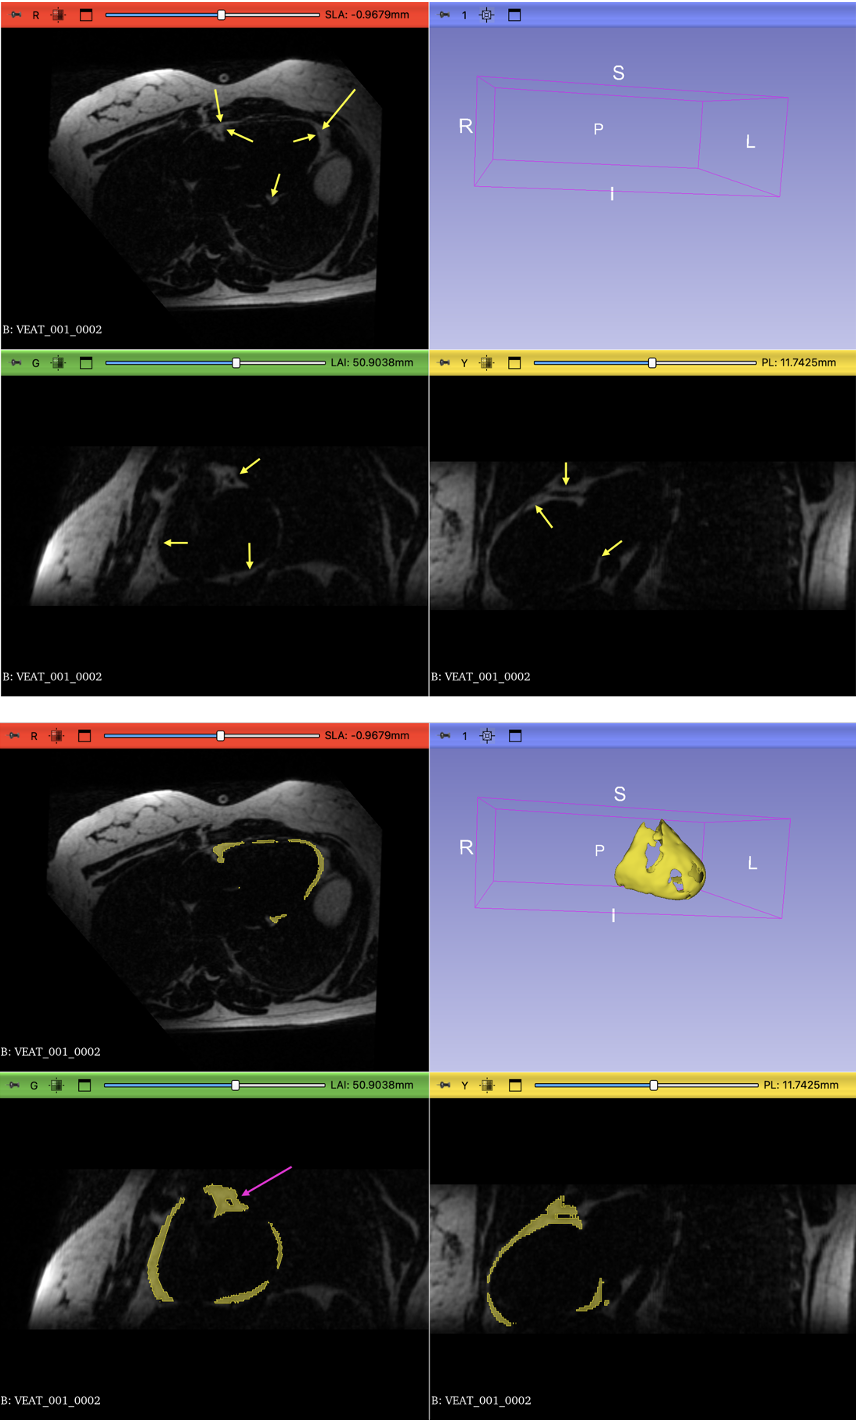

Figure 2: (a) Interobserver comparison between two readers (O1 vs. O2), (b) comparison between the nnU-Net model and reader O1, and (c) intraobserver comparison for reader O1. The top row shows Pearson correlation plots, and the bottom row shows the corresponding Bland–Altman plots. The limits of agreement in the Bland–Altman plots were defined as the mean difference ± 1.96 × the standard deviation of the differences.